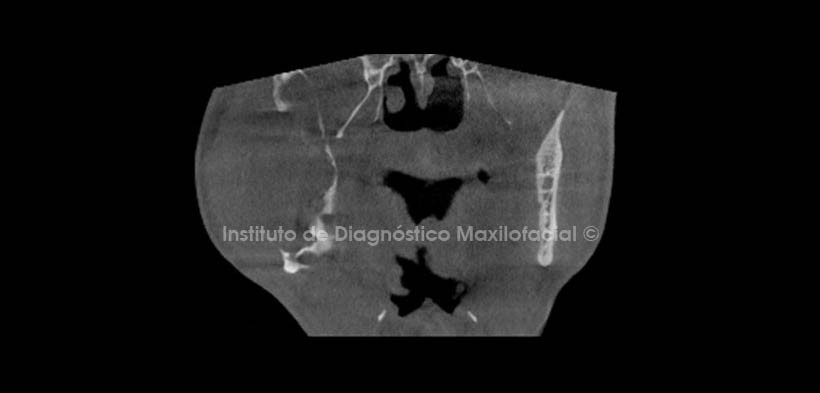

En cortes coronales apreciamos expansión de tablas a nivel de rama y cuerpo mandibular; Se observa erosión marcada en tabla ósea vestibular y desplazamiento caudal del conducto dentario inferior, el cual se encuentra sobre la basal mandibular a nivel de molares. (Fig. 3, 4 y 5)